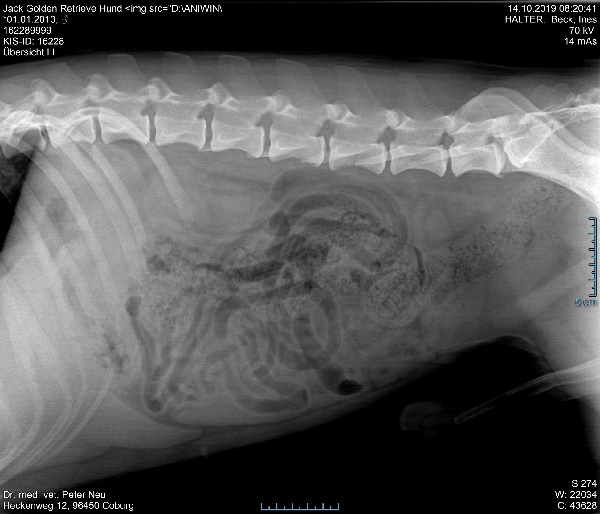

Das ist unser Patient “Jack”.

Golden Retriever, ein Pfundskerl

echter Buddy

Allgemeine Untersuchung 16€, FNA Biopsie, Blutbild 24€, Klinische Chemie 48€, Röntgen (2x ) 96€, Fremdkosten Zytologie 59€ sind brutto 302€